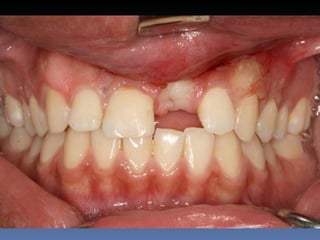

Maurício Zanetti

Idade – 47 anos

Sexo – Masculino

Raça – Caucasiana

ASA – II

Data- 25-04-2012

Diagnóstico: Desdentado parcial

pré-maxila.

Plano de tratamento: Reabilitação pré-maxila com

instalação de 2 implantes endo-ósseos (1.1,.2.2), para

reabilitação protética fixa.